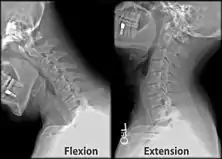

Cervical lines are annotations used in medical imaging of the cervical vertebrae, here seen on X-ray and CT, respectively. Incongruencies indicate cervical fracture, spondylolisthesis and/or ligament injury.